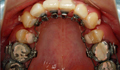

●主 訴 ― 頭痛や肩こり・歯ぎしりが、ひどく、噛み合わせが悪い。

●治療期間 ― 矯正 約5ヶ月 アゴの治療 約3ヶ月

●治療内容 ― コルチコトミー手術を併用したスピード矯正と整体による理学療法 |

スピード矯正をして約8年経ちましたが、

今も安定しています。

これもコルチコトミーの効果だとおもいます。 |

| 治療後6年目 |